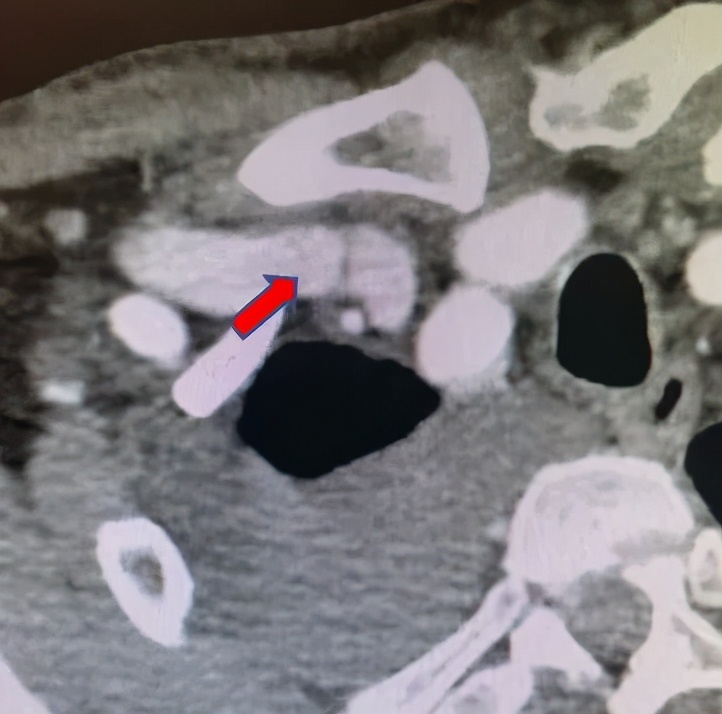

张东亮主任耐心听完患者的叙述,给出了诊断: “肿胀手综合征” 。肿胀手的主要原因是自体动静脉内瘘成型后,静脉发生动脉样改变,管腔内静水压力升高,当静脉血液回流不畅时就会导致压力进一步升高,从而形成患侧手臂显著增粗的病症,这在起搏器植入的血透患者中,发生率更高。张主任立刻为老李安排检查:首先是超声明确内瘘吻合口内径,发现血管流量尚可,静脉弓汇入锁骨下静脉处相对性狭窄伴迂曲。随后又进行了上肢及深静脉CT三维重建(CTA+CTV),发现主要病变为锁骨下静脉汇入头臂静脉处静脉瓣增生狭窄(如下图)

病变明确了,张主任当机立断,立即进行介入手术。张东亮主任医师与付晨主治医师在新建成的新龙泽院区介入手术中心进行了局麻下经皮穿刺血管内介入治疗。张主任凭借丰富的经验、娴熟的手法很快将超滑导丝通过病变部位,10mm高压球囊将狭窄部位扩张至无回弹,再次造影确认,心细的张主任又发现了新的端倪——近心端静脉还有一处狭窄!此前这一病变在CTA+CTV结果中并没有发现,张主任毫不犹豫,球囊再前进50mm、*压打**扩张,再次造影复测,血流通畅、侧支循环和返流消失。